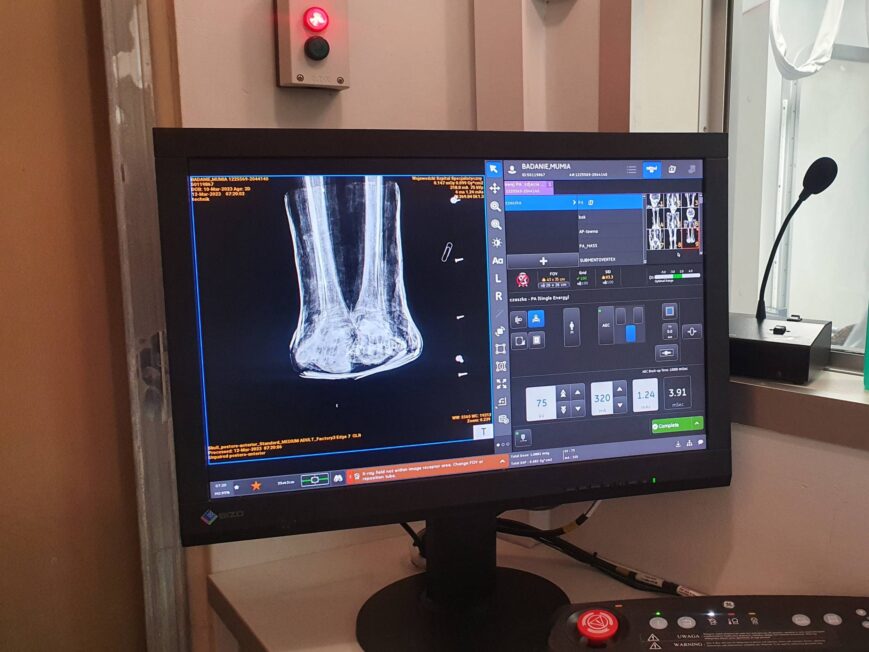

Badania radiologiczne przeprowadzono z użyciem aparatu rentgenowskiego DR GE Optima XR 646 oraz tomografu komputerowego Canon Aquilion Prime ST, czyli jednego z najbardziej zaawansowanych urządzeń tego typu dostępnych w Polsce. Urządzenia te pozwalają uzyskać serię bardzo dokładnych przekrojów ciała, a następnie połączyć je w trójwymiarowy obraz. Dzięki temu naukowcy mogli „zajrzeć” pod bandaże i do wnętrza ciała, nie naruszając ani jednego włókna tkaniny.